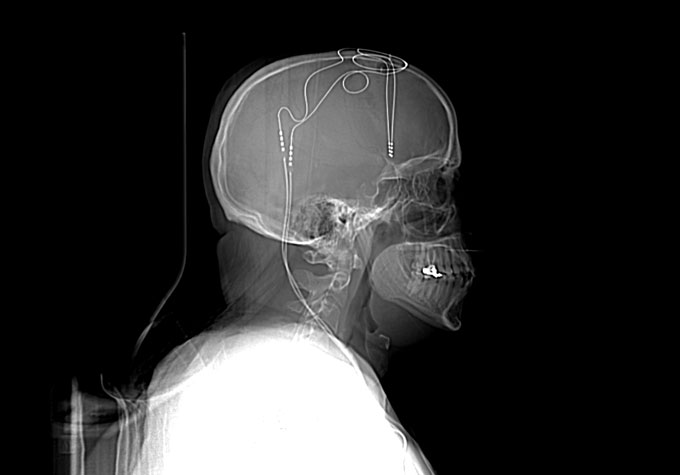

There, at Mount Sinai’s hospital just southwest of Central Park, surgery team members screwed Jon’s head into a frame to hold it still. Then they numbed him and drilled two small holes through the top of his skull, one on each side. Through each hole, a surgeon plunged a long, thin wire dotted at the end with electrodes deep into his brain. The wiring, threaded under his skin, snaked around the outside of Jon’s skull and sank down behind his ear. From there, a wire wrapped around to the front, meeting a battery-powered control box that surgeons implanted in his chest, just below his collarbone.

During the surgery and in the days after, doctors sent small pulses of electricity into Jon’s brain. In ways that are still unclear, this electrical tinkering changes the messages that move between different brain regions. The doctors and researchers had what seems like a bold goal: They wanted these pulses to pull Jon out of the darkness of depression.

Jon is one of dozens of people in the United States currently in clinical trials that aim to heal mental disorders with brain implants. The technique is called deep brain stimulation, and it’s built on the scientific premise that electrical stimulation can reset brains that are in the grip of powerful and devastating psychiatric disorders such as depression, obsessive-compulsive disorder and post-traumatic stress disorder.